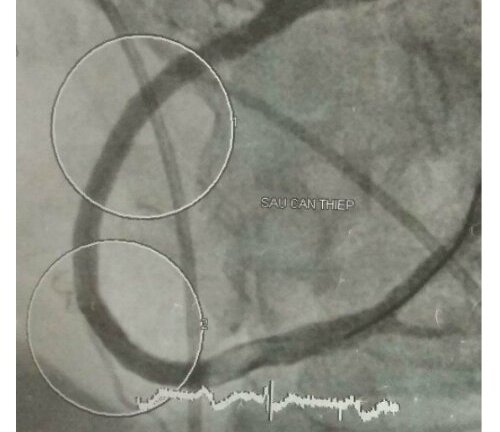

Bác sĩ nhiều viện hợp sức cứu đồng nghiệp bị nhồi máu cơ tim

Bác sĩ 65 tuổi về hưu bị nhồi máu cơ tim, tình trạng nguy cấp khi can thiệp mạch vành được đồng nghiệp ba viện hợp sức cứu sống.